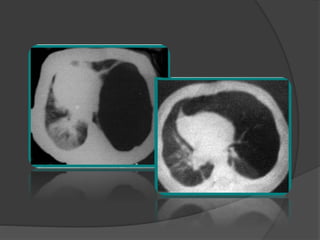

 Le scanner thoracique: confirme le diagnostic

Le lobe atteint = hyperclair et hypovascularisé

 Plus sensible:

 Aspect caractéristique des structures vasculaires

étirées et grêles

 Localisation

 Étiologie

 Diagnostic différentiel